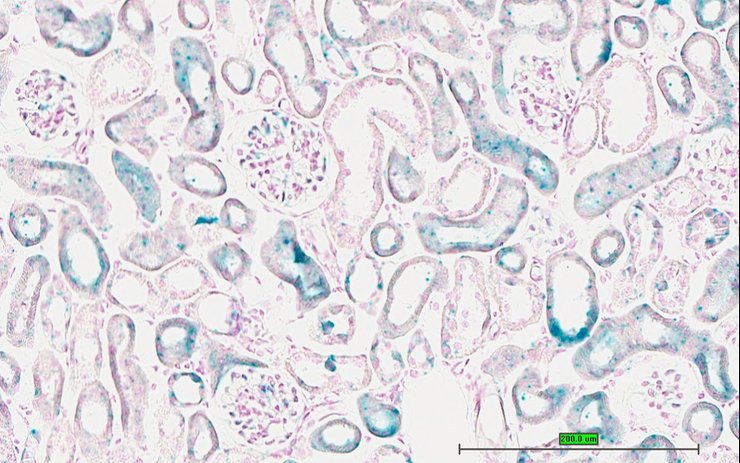

TS28: metanephros Present UC Davis_1873109 kidney

Specimen UC Davis_1873110: postnatal adult; Cox15tm1.1(KOMP)Vlcg/Cox15+ (more )

Structure Level Pattern Image Note

TS28: metanephros Present UC Davis_1873110 kidney

Specimen UC Davis_1873111: postnatal adult; Cox15tm1.1(KOMP)Vlcg/Cox15+ (more )

TS28: metanephros Present UC Davis_1873111 kidney